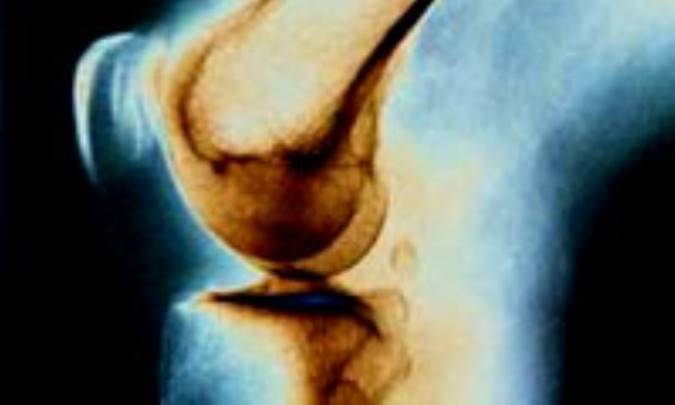

بيشتر نوجوانان و جوانان تصور مي کنند آرتريت( آرتروز يا التهاب مفصل) فقط به پدربزرگ ها و مادربزرگ ها مربوط مي شود، اما واقعيت آن است که همه رده هاي سني ممکن است به اين بيماري مبتلا شوند، به خصوص نوع خاصي از آرتريت که مخصوص افراد زير 17 سال است و به عبارتي بيشتر گريبان نوجوانان و جوانان را مي گيرد. بيماري آرتريت روماتوييد در عده اي از نوجوانان و جوانان بروز مي کند که موجب ناتواني آنان شده و در بزرگسالي ممکن است موجب ابتلاي زودهنگام آنها به آرتروز شود. واژه روماتوييد به بيماري خاصي اشاره مي کند که عضلات، تاندون ها، مفاصل، استخوان ها يا اعصاب را تحت تأثير قرار مي دهد. آرتريت به معني التهاب غشاي سينوويال است که مفاصل را مي پوشاند. در التهاب اين غشا، مايع توليد مي شود و مفاصل سفت، متورم، دردناک و حين تماس کاملاً گرم مي شود. اين بيماري شايع ترين نوع آرتريت ميان کودکان و نوجوانان است و معمولاً در سنين 2 تا 16 سالگي تشخيص داده مي شود. نشانه هاي اين بيماري چند بار طي بروز بيماري نمود پيدا کرده و محو مي شوند. اين بيماري مي تواند علاوه بر مفاصل و بافت هاي اطراف، روي چشم ها، کبد، قلب و ريه ها هم تأثير بگذارد. گاهي نشانه ها مختصر است و برعکس در بعضي شرايط آن قدر حاد است که به رشد فرد صدمه مي رساند. نوجوانان مبتلا به اين بيماري دچار درد و سفتي مفاصل هستند که از روزي به روز ديگر يا از صبح تا عصر تغيير مي کند. در دوره هايي خاص، بيماري نمود بسيار شديدتري پيدا مي کند . اين بيماري مزمن است و حدود شش هفته يا بيشتر طول مي کشد و مي تواند ماه ها و سال ها ادامه پيدا کند. گاهي علايم و نشانه ها خود به خود محو شده و يک دوران نهفتگي و سرکوب بيماري به وجود مي آيد که شايد ماه ها و سال ها ادامه پيدا کند. در نهايت نوجوانان مبتلا وارد مرحله اي مي شوند که بيماري کاملاً محو شده است. گاهي اين بهبود بدون هيچ مشکل مفصلي است و گاهي هم مشکلاتي براي مفصل ايجاد مي شود که ماندگار است.

تنها چهار مفصل يا کمتر درگير مي شوند که به طور معمول مفاصل بزرگ تر مثل زانو مبتلا هستند. در اين حالت امکان ابتلاي چشم ها هم وجود دارد. به همين دليل حتي در صورت فعال نبودن بيماري، معاينه چشم ها در اين نوع از بيماري ضروري است.